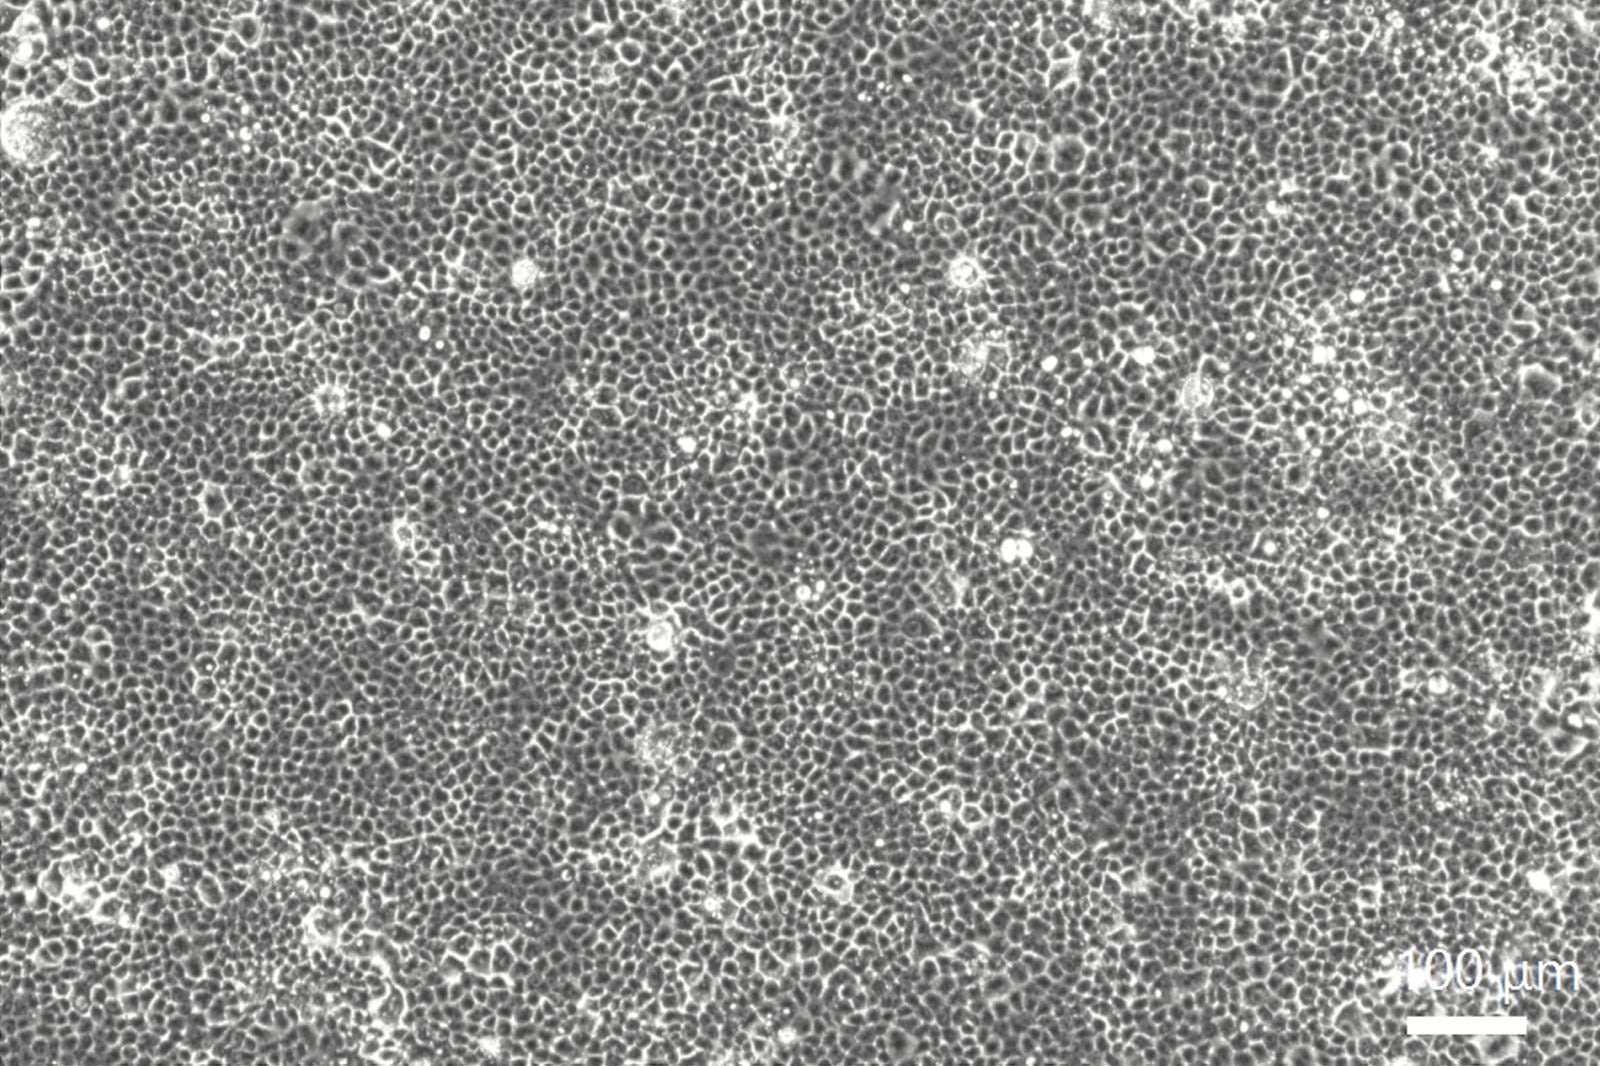

パナソニックは、ナノイー(帯電微粒子水)技術について、2020年7月に新型コロナウイルスに対する抑制効果(※2)、2021年11月には新型コロナウイルス変異株4種に対する抑制効果(※3)、2022年3月には約6畳(24立方メートル)の試験空間における新型コロナウイルスに対する抑制効果(※4)を実証しています。また、ナノイー(帯電微粒子水)を曝露した新型コロナウイルスをVero細胞(※5)に接種しても細胞死が起こらないことが明らかとなっており、感染が起こらないことが示唆されています。しかし、これまでは、ナノイー(帯電微粒子水)が新型コロナウイルスにどのように作用して不活化しているのか、明らかになっていませんでした。

そこで、ナノイー(帯電微粒子水)による新型コロナウイルスの不活化メカニズムに焦点を当て、ナノイー(帯電微粒子水)の曝露有無によるウイルスの構成成分ごとの影響や、細胞へのウイルスの結合量を測定しました。その結果、ウイルスを構築する脂質二重膜やタンパク質、ゲノムRNAと多段階で作用する様子が確認されました。さらに、ナノイー(帯電微粒子水)を曝露したウイルスは細胞への結合能力が失われることで感染が抑制されることが示唆され、ナノイー(帯電微粒子水)による新型コロナウイルスの不活化メカニズムの一部が明らかになりました。なお、今回の検証は密閉された試験空間での結果であり、実使用空間における効果を検証したものではありません。